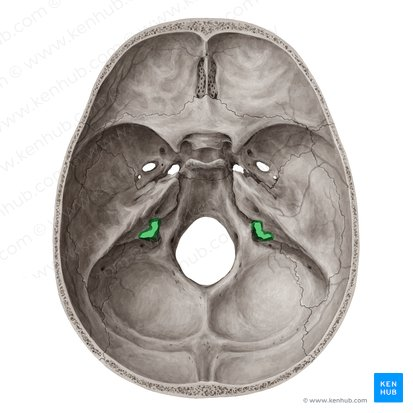

Jugular foramen (for internal jugular vein and nerves)

Internal acoustic meatus (for passage of the auditory nerve)

Carotid canal (for internal carotid artery)

Sella turcica (holds pituitary gland - “Turk’s saddle”)

Cribriform plate of the ethmoid bone (notice olfactory formina in it - for olfactory nerves. Crista galli “rooster’s comb” dura mater attaches here)

Optic canals (optic nerve)

Optic canals (optic nerve)